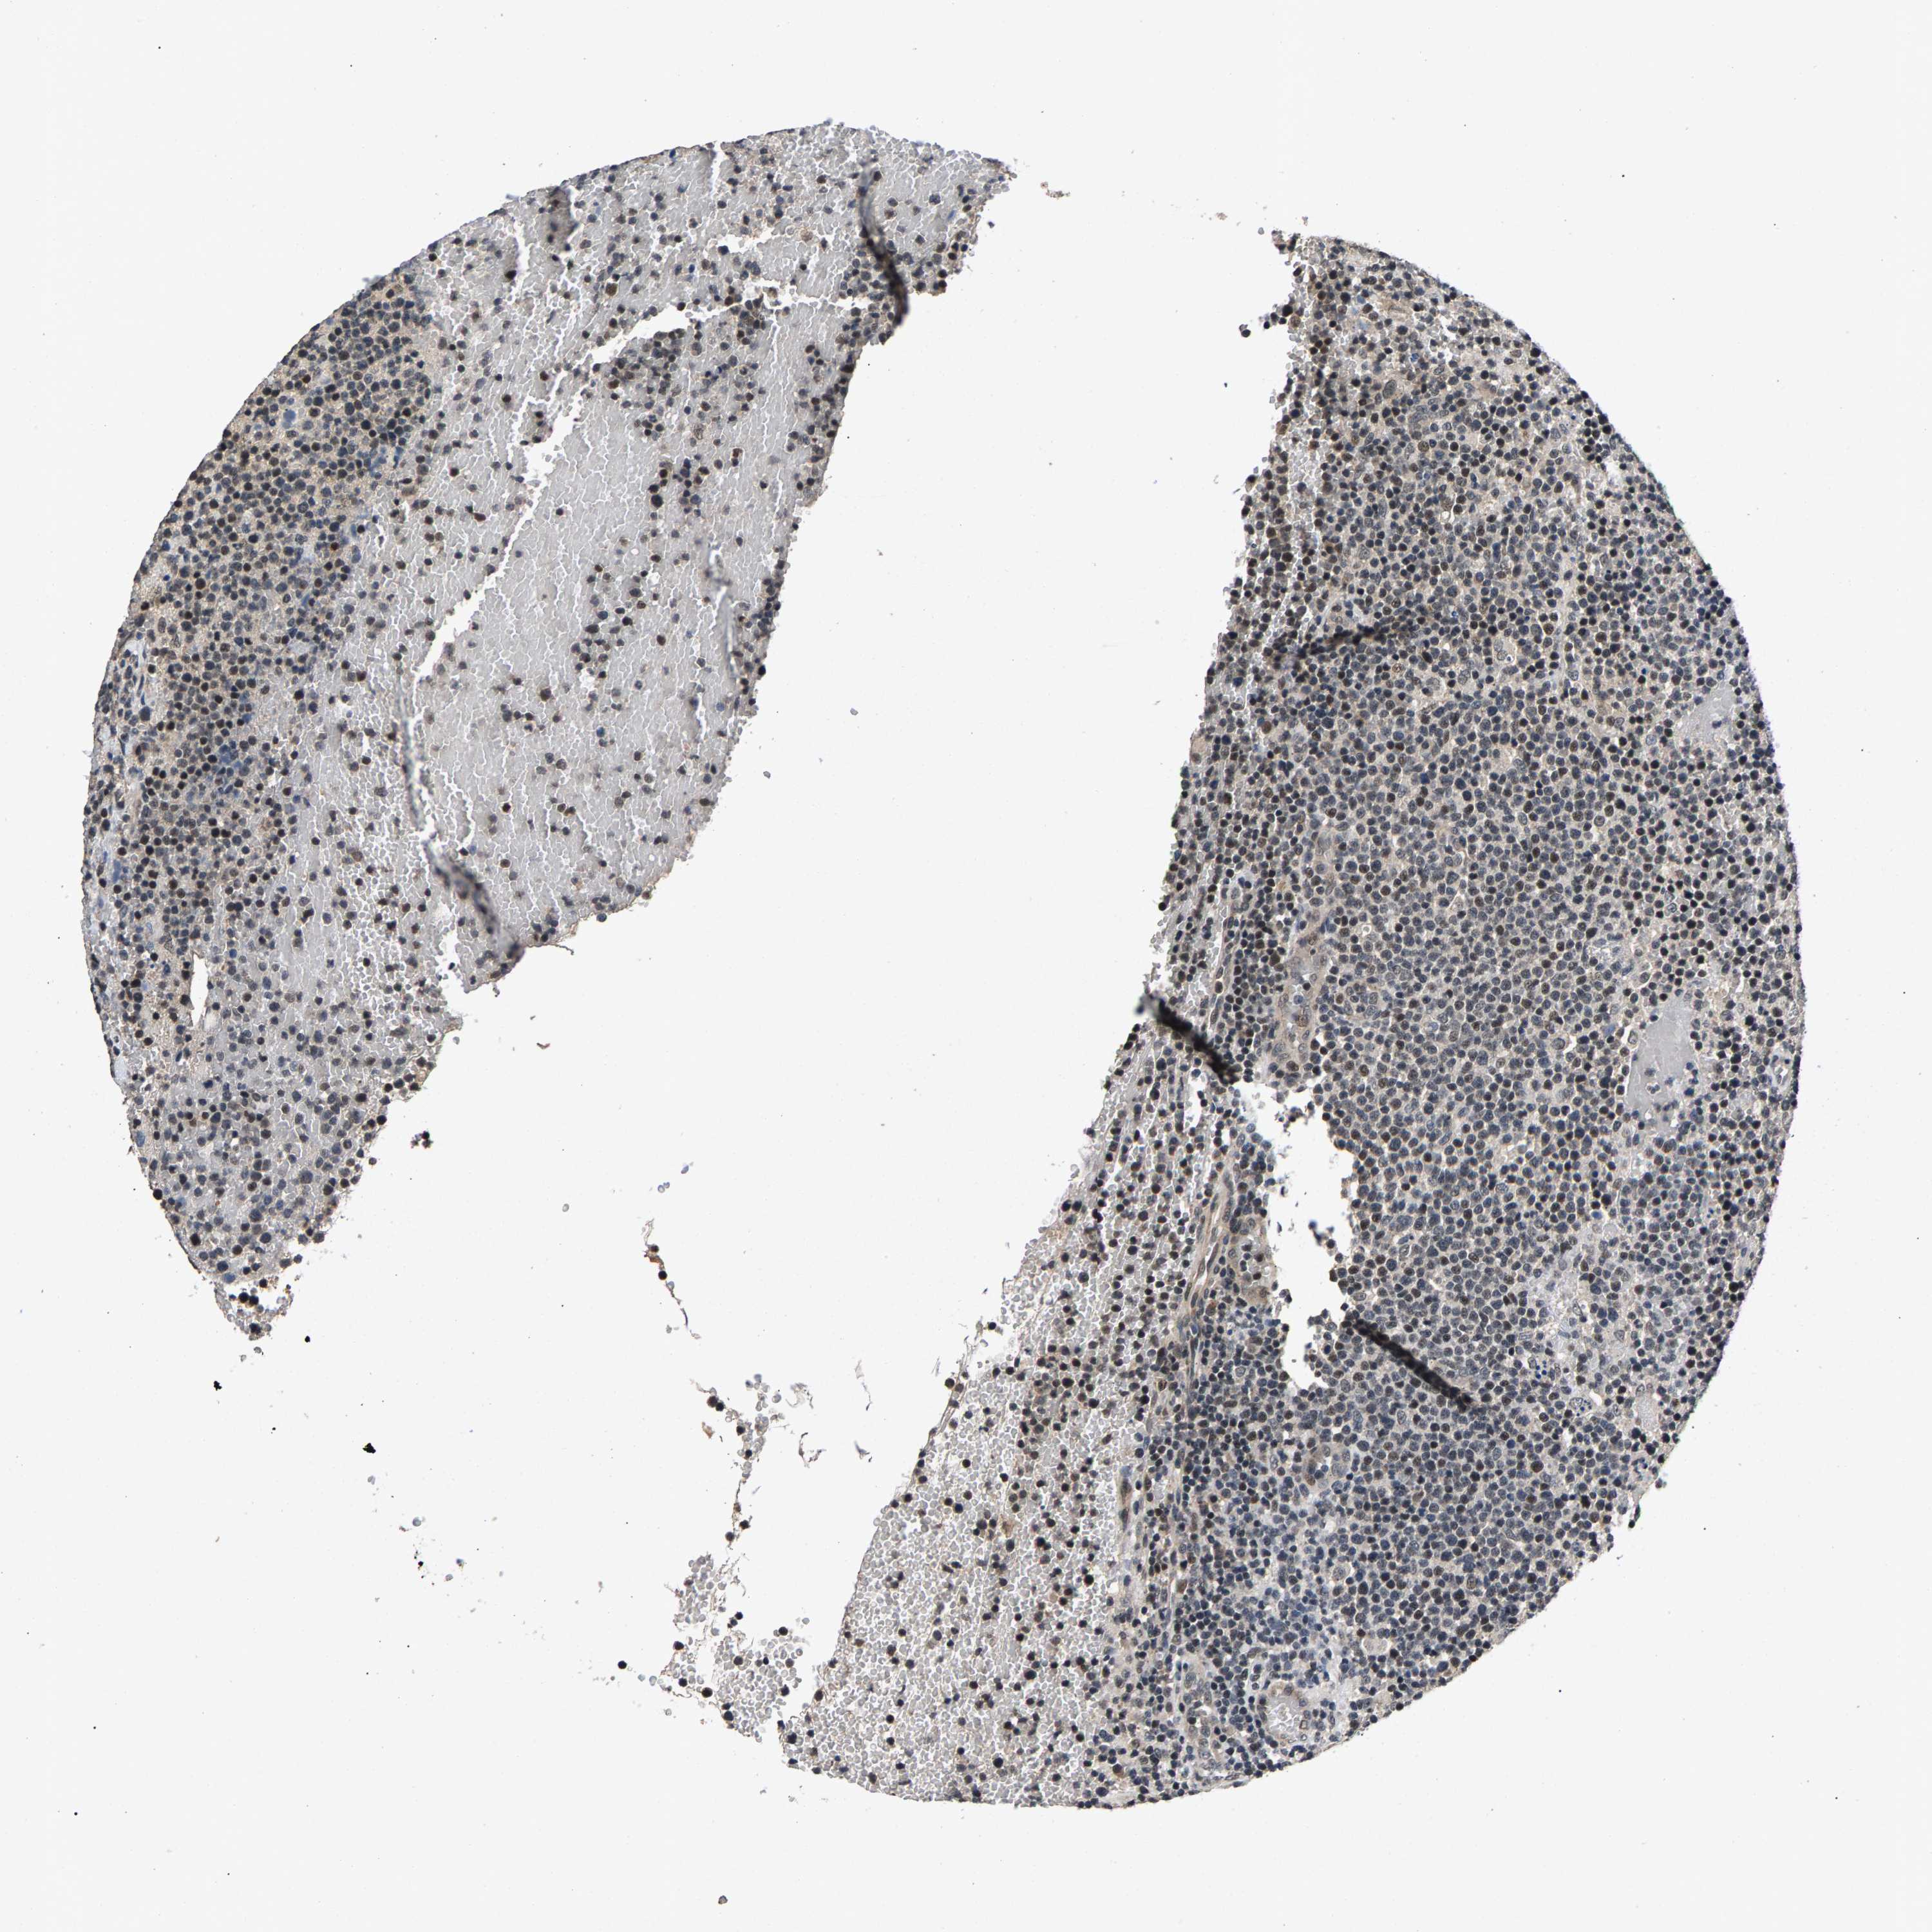

CANCER LYMPHOMA Show tissue menu

LYMPHOMA - Protein expressioni

A mouse-over function shows sample information and annotation data. Click on an image to view it in a full screen mode. Samples can be filtered based on level of antibody staining by selecting one or several of the following categories: high, medium, low and not detected. The assay and annotation is described here.

Each image is clickable and will lead to virtual microscopy that enables deeper exploration of all samples and also displays staining intensity scores, fraction scores and subcellular localization as well as patient and tissue information for each sample.

Antibody HPA019232

Antibody HPA021497

Antibody HPA021768

Hodgkin's disease, NOS

Malignant lymphoma, non-Hodgkin's type, High grade

Malignant lymphoma, non-Hodgkin's type, Low grade